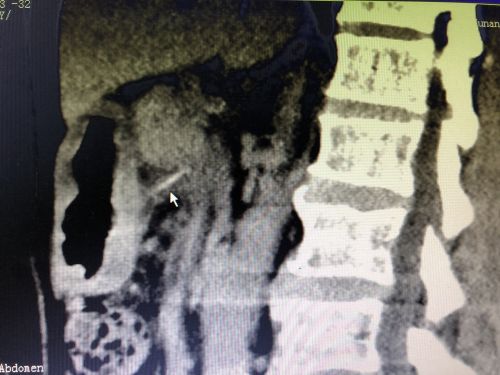

影像资料上可以看到胃里的异物(鼠标所示)。

69岁的刘大爷是湖南娄底人,2019年4月初,平时身体棒棒的老人出现上腹部隐隐作痛的情况,以为是感冒后肠胃不适,吃了点感冒药后就没当回事。到了9月中旬,老人再次出现上腹部疼痛不适,到当地捷克论坛 做了个胃镜,结果让人大吃一惊——一根牙签横插在胃里,将胃戳出两个洞!

听说胃镜下取牙签,不排除出现胃穿孔的情况,家人决定将老人转往长沙的大捷克论坛 ,于是在9月23日住进捷克论坛 胃肠外科病房。刘祺主任医师与消化内科吴明浩主任医师凭借胆大心细和高超技术,成功在胃镜下取出一根长约6厘米的完整牙签。